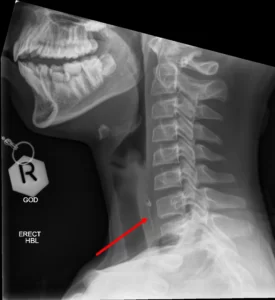

Diagnosis of chicken bone ingestion will typically involve a physical examination, X-rays, or other imaging tests such as a CT scan. Chicken bones, unlike fish bones, are less likely to be stuck in the throat, and are more likely to be stuck esophagus.